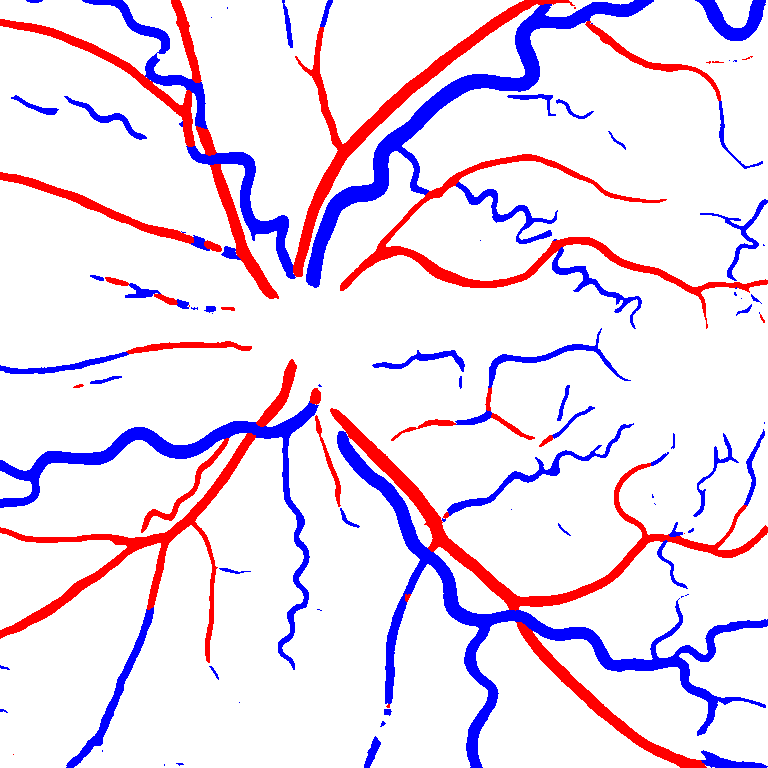

(a) Reference (b) Output (c) Width Map

As reported in Table IV, we compared the SegRAVIR model against competing deep learning-based segmentation approaches on the RAVIR dataset. Evidently, SegRAVIR outperforms these methods as judged by all metrics for artery and vein classes with a healthy margin. In terms of Dice score, SegRAVIR outperforms CE-NET, IterNet and AG-Net by , and for artery segmentation and by , and for vein segmentation, respectively. Fig. 4 presents a qualitative comparison of the semantic segmentation outputs of SegRAVIR, CE-Net, and U-Net. Specifically, SegRAVIR yields more accurate vessel topology (i.e., thickness and orientation) segmentation with higher pixel-wise classification accuracy.

Table V presents quantitative performance benchmarks of SegRAVIR and other competing approaches for retinal artery and vein classification on the RITE dataset [11]. SegRAVIR outperforms previous state-of-the-art approaches in terms of accuracy, sensitivity, and specificity. Fig. 5 provides a qualitative comparison between segmentation outputs of SegRAVIR and the method of Hemelings et al. [40] on the RITE test set.

Table VI presents a quantitative comparison of the measured diameters using the segmentation outputs of SegRAVIR and competing approaches. Using the pixel-wise annotated masks, the reference average diameter of the arteries and veins in the test set of the RAVIR dataset were measured as and , respectively. According to our analysis, SegRAVIR can accurately measure the diameter of the vessels and it achieves the smallest MAPE among the competing approaches. Specifically, in comparison to CE-Net, Iter-Net, and DU-Net, respectively, SegRAVIR is on average , and more accurate in terms of MAPE for the measured diameter of arteries and , and in terms of MAPE for the measured diameter of veins. Fig. 6 presents qualitative comparisons of reference and SegRAVIR estimated diameter maps.

(a) (b) (c)

(a) (b) (c)